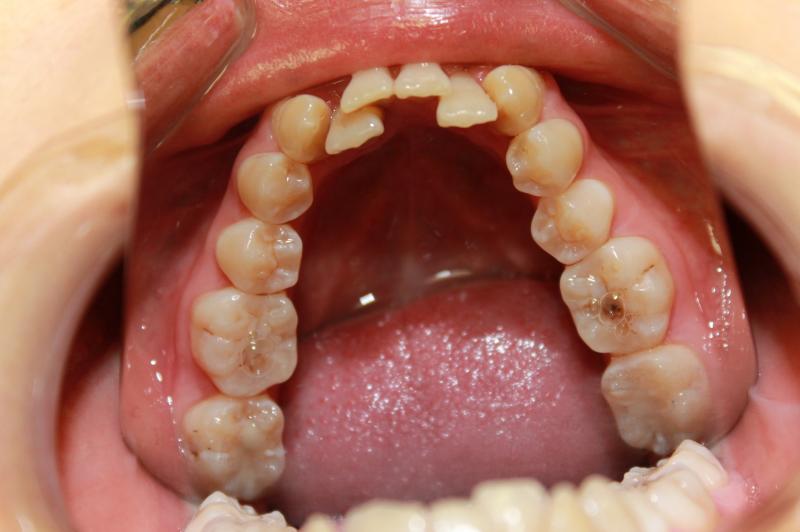

INVISALIGN - 13 months, 1 lower tooth removal, 1 series of aligners to align teeth and create the proper amount of space for 2 cantilever bridge to replace congenitally missing cuspids. COSMETIC DENTISTRY - 2 porcelain cantilever bridges and cosmetic bonding to reshape incisors and close gingival spaces. TOTAL TREATMENT TIME, 15 months

Cosmetic Dentistry, Mid-line Asymetry, Missing Teeth, Severe Crowding